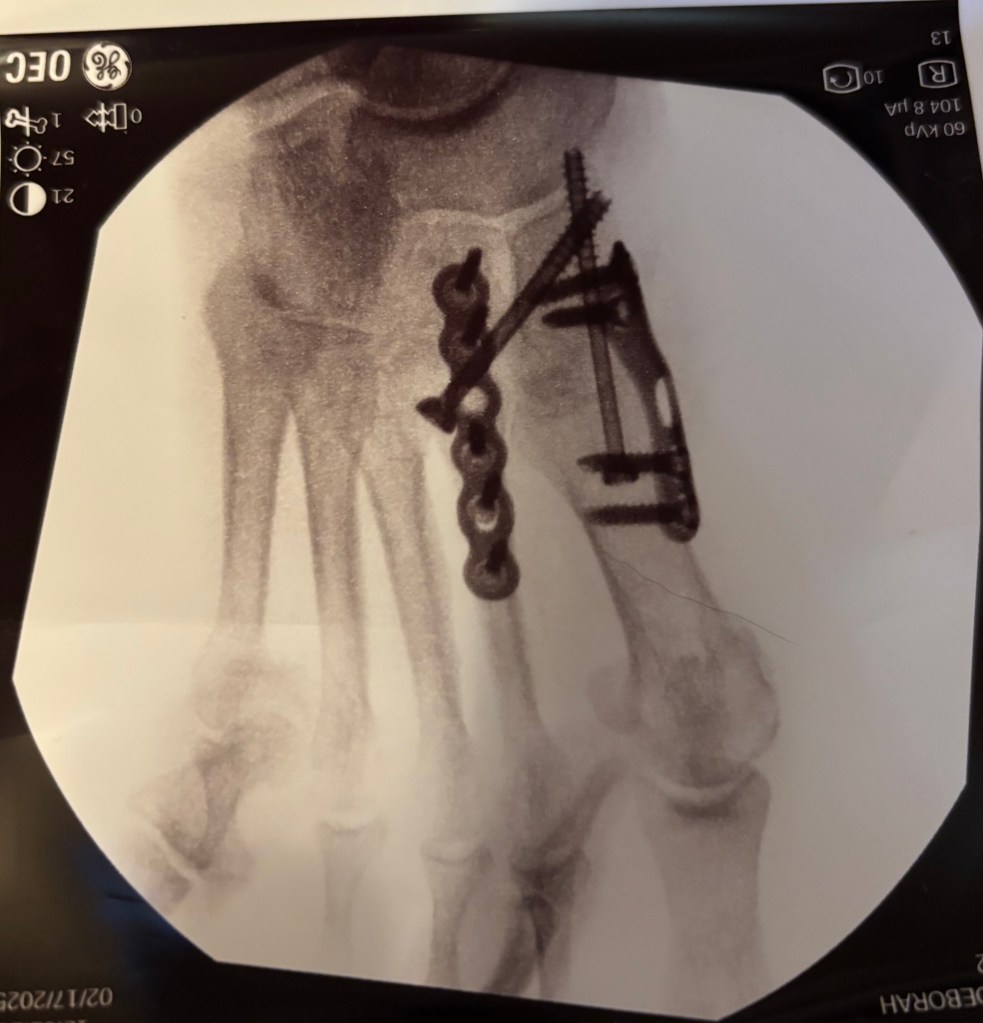

With this much hardware in my foot, I’m not about to go walking around until my doctor says I can. No photography. No sewing. No cleaning out the junk room. No baking. If we do go somewhere, I have to make sure I don’t drink anything so I don’t have to use a bathroom. I’ve discovered the hard way that the handicap stall in public restrooms doesn’t accommodate wheelchairs.